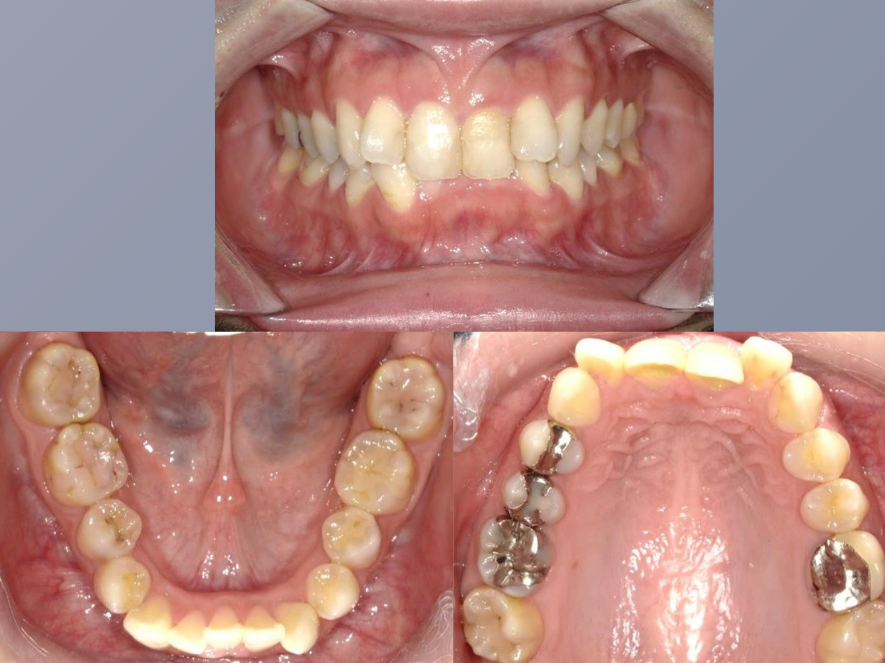

治療後

| 年齢・性別 | 20代・女性 |

|---|---|

| 主訴 | 前歯の歯並びが気になる。 |

| 期間 | 2年4ヶ月 |

| 費用 | 1,001,000円(税込) |

| 治療内容 | 矯正の前半に舌側から付ける装置で、歯の裏側に装着するため他人からは全く見えません。 顎の位置を正常な位置にもっていくという一番大切な治療を平行して行い、舌房や気道を広げます。 歯並びだけではなく健康な口腔内を作り出していくことが可能です。 |